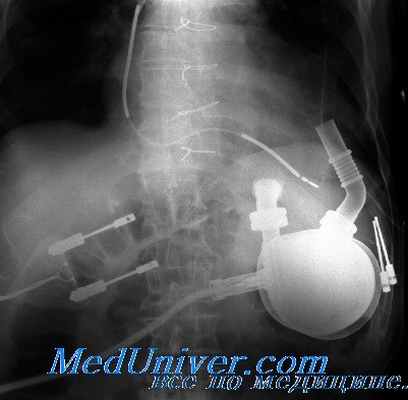

Фильтр, который устанавливают в нижнюю полую вену (кава-фильтр) нужен для того, чтобы уловить тромбы и не дать им оказаться в легочной артерии. Новые модели кава-фильтрав являются съемными и их можно ставить на период особенно высокого риска тромбозов, или затем оставить, как постоянный фильтр (7,8). Фильтр рекомендуется устанавливать пациентам с подтвержденным венозными тромбоэмболическими осложнениями, у которых имеются серьезные проблемы с приемом полных доз антикоагулянтов ( например, пациенты с кровотечениями или после недавно выполненной нейрохирургической операции). Съемные фильтры можно использовать у пациентов со временными противопоказаниями к терапии антикоагулянтами, например, при травме (12).

Тромбоэмболия — серьезная проблема для любого пациента с УВК из-за взаимодействия крови и устройства. Распространенность случаев эмболии колеблется от 2 до 47%; наиболее часто встречается мозговая эмболия, но методы диагностики эмболии в разных исследованиях разнообразны. УВК пульсирующего типа HeartMate имеют самую низкую частоту тромбоэмболических осложнений из всех УВК, несмотря на то что пациенты не получают варфарин (вероятно, формирование неоинтимы уменьшает эмболизацию).

В других случаях необходимо применение гепарина в раннем послеоперационном периоде, а впоследствии варфарина и антитромбо-цитарных средств, таких как аспирин или клопидогрел.